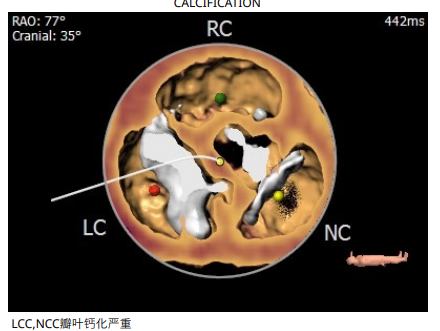

术前周浩教授带领团队对这位患者进行了详细的分析,从CT分析结果显示,患者的瓣环直径为25.1mm,结合患者瓣叶钙化等情况,符合美敦力Evolut PRO 29mm瓣膜选型要求。难点在于患者左右瓣叶钙化严重,钙化积分达到了1500,经讨论决定术中进行23mm球囊预扩张,保证系统顺利跨瓣及释放。术中采用了全球领先的Cusp Overlap瓣膜植入技术,实现更精准地定位瓣膜深度,减少对患者传导系统的影响。